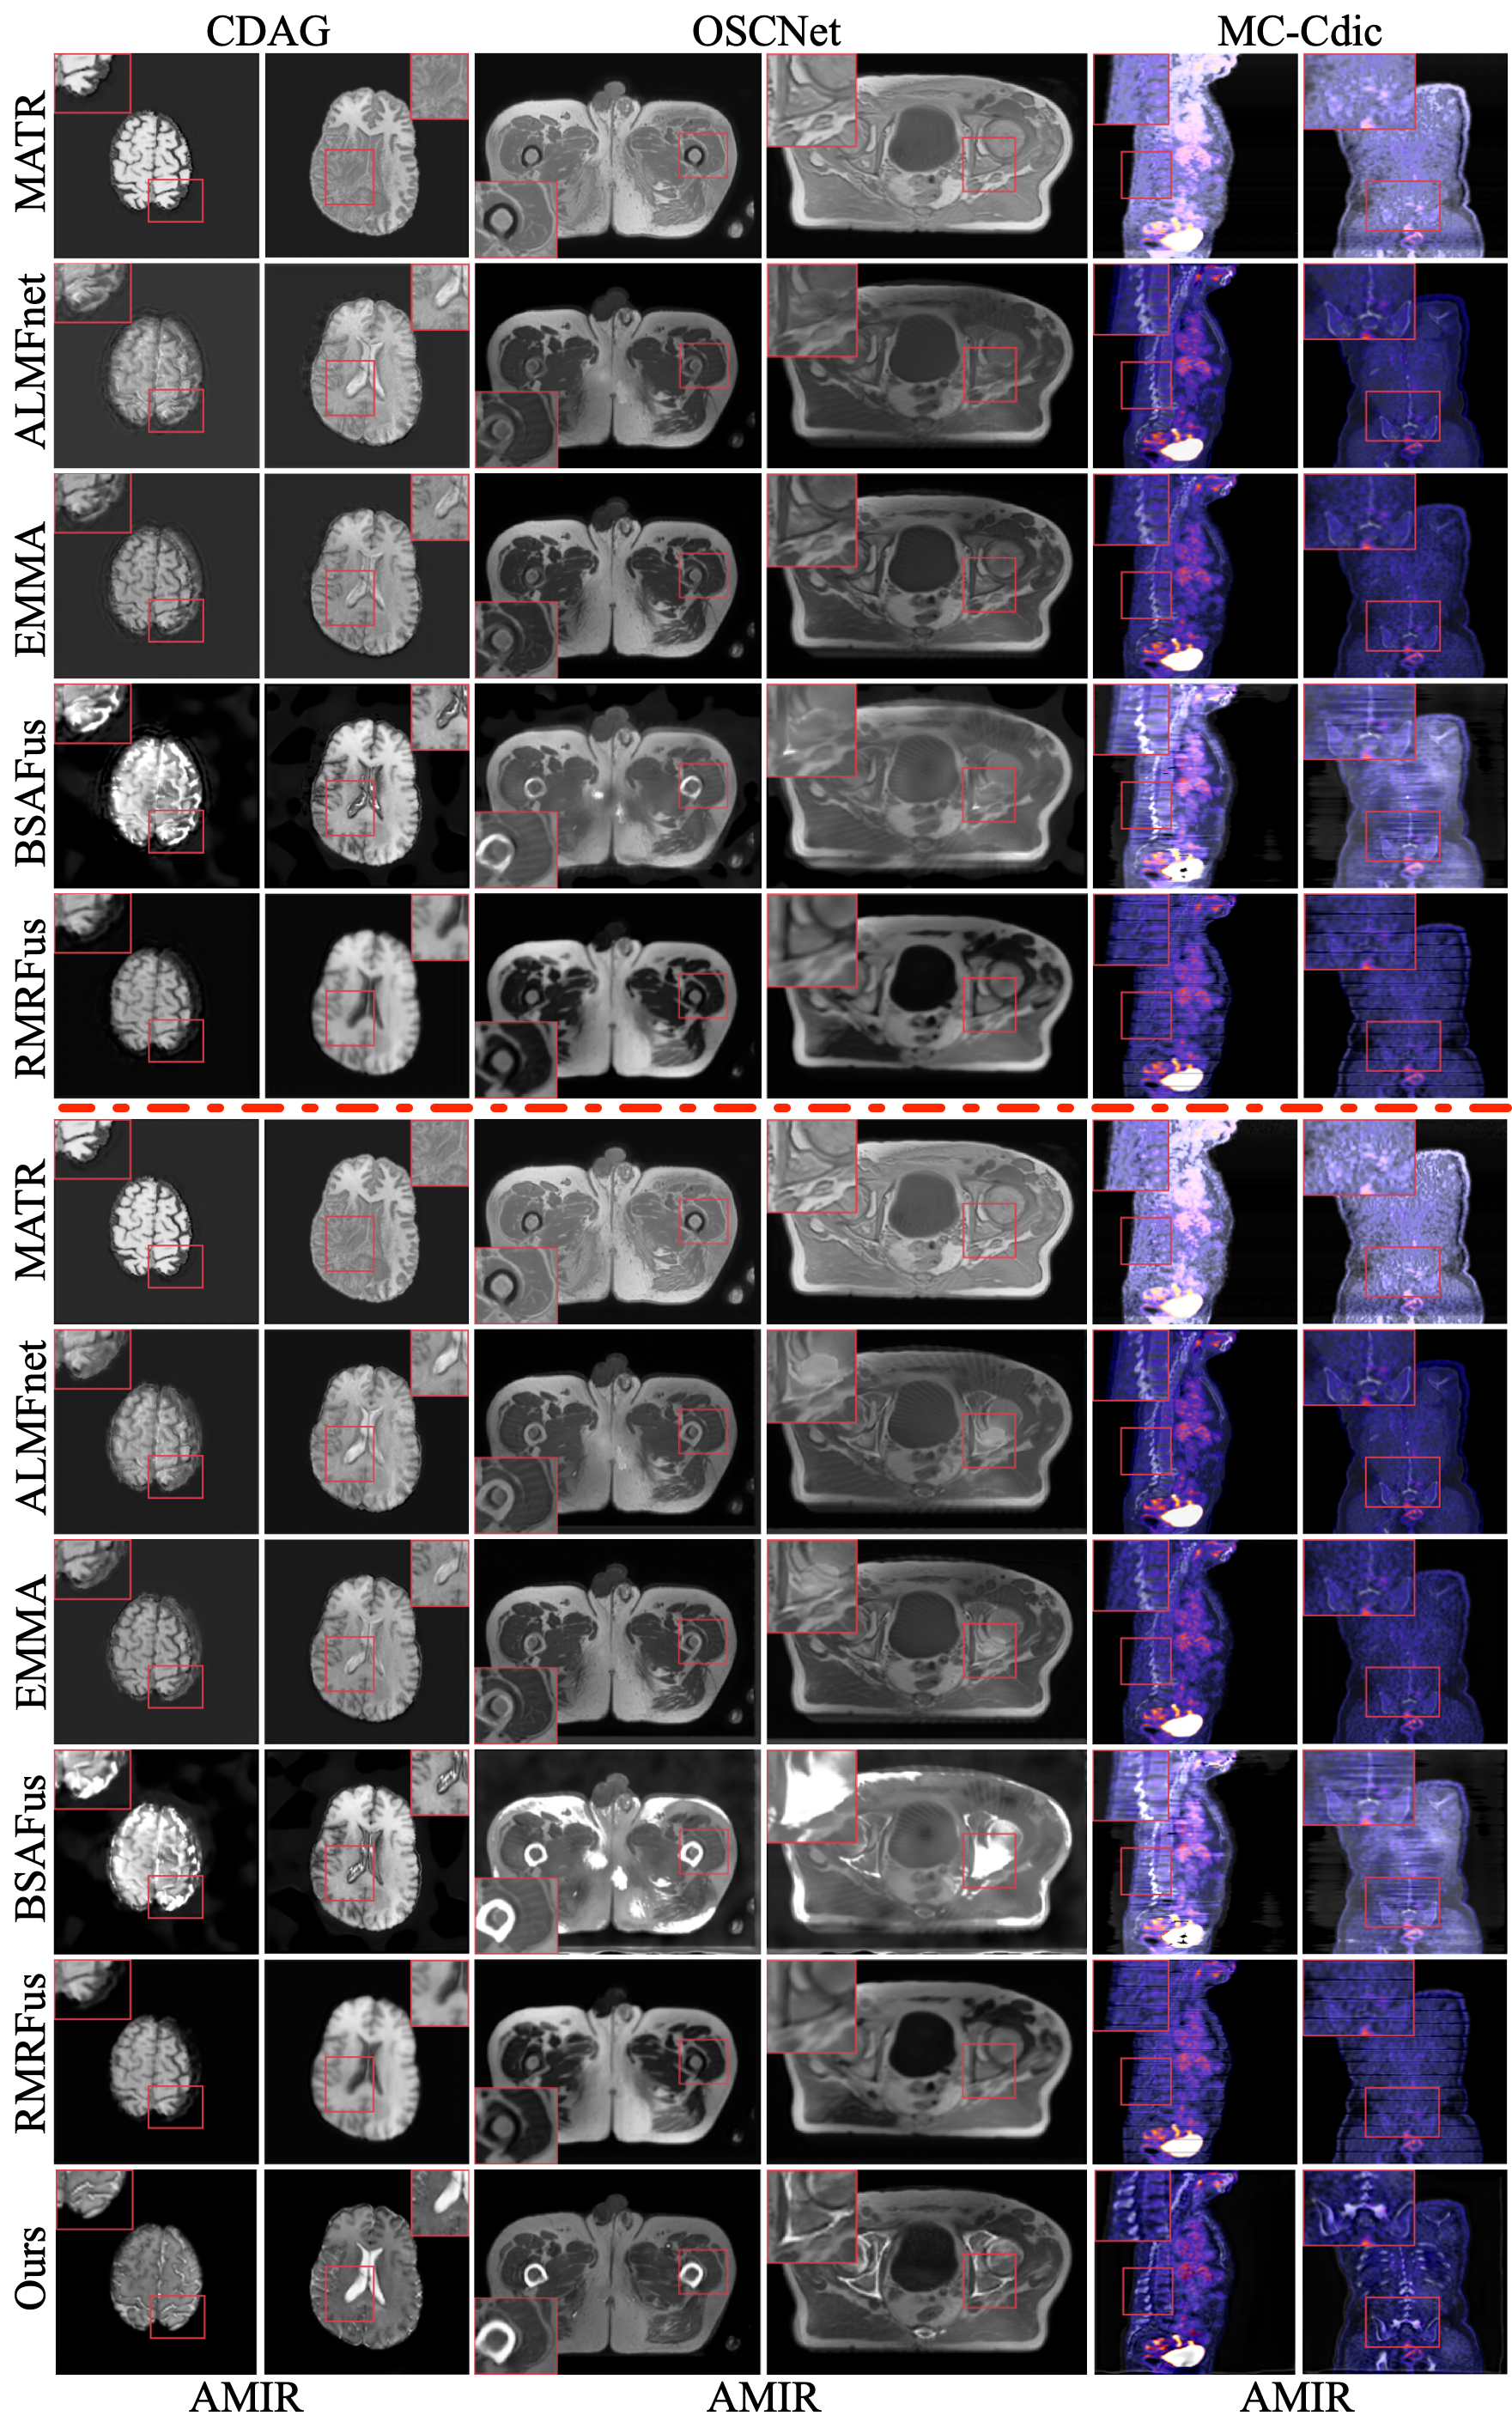

Refer to caption

Figure 4: Visual Comparison of Fusion Results. The first column shows reference images without degradation, and the second column shows high-quality labels. The third and fourth columns present misaligned degraded images and their distortions. Columns 5 to 15 display results from different fusion methods. The image restoration methods to the right of the red line are shown on the right side of the figure, while those to the left are shown on the left side.

Comparison of Results on BraTS2020. The MRI-T2 imaging process is often time-consuming, during which slight patient movement may introduce inevitable motion artifacts. To assess our method’s performance in image fusion when source images contain motion artifacts, we compare it against a multi-stage combination strategy on the BraTs2020 dataset. For the comparison method, we first restore the degraded MRI-T2 images using MC-CDic and AMIR, respectively. Next, we align the restored images with MRI-T1 images using CorrMLP. Finally, we apply five image fusion techniques to generate the final fused images. The top two rows of Figure 4 present the fusion results of different methods. It can be observed that our method demonstrates significant advantages in spatial alignment, motion artifact elimination, contrast enhancement, and detail preservation. Table 1 presents a quantitative comparison of each method’s performance on the dataset. The results indicate that our method achieves the highest average score on all five fusion metrics while significantly reducing computational cost compared to other methods.

Comparison of Results on SynthRAD2023. Metal implants or foreign objects are commonly found in patients, which inevitably introduce metal artifacts in CT images, degrading fusion quality. To assess our method’s fusion performance on images degraded by metal artifacts, we performed comparisons on the SynthRAD2023 dataset. Specifically, we first restored the CT images affected by metal artifacts using OSCNet and AMIR. Then, following the same processing pipeline as for the BraTs2020 dataset, we employed CorrMLP for image registration. Finally, we applied five fusion methods to generate the final fused images. The third and fourth rows of Figure 4 illustrate the visual fusion results of each method on this dataset. As observed, our method effectively preserves structural integrity and contrast while mitigating feature mismatches and metal artifacts. Table 2 presents a quantitative comparison, showing that our method outperforms all others across all metrics while maintaining significantly lower computational cost.

Comparison of Results on FDG-PET/CT. To reduce radiation exposure in PET imaging, low-dose PET images often suffer from noise. To assess our method’s fusion performance on noisy PET images, we compared it with multi-stage approaches. Specifically, we first restored the degraded PET images using CDAG and AMIR, then performed registration and fusion following the same procedure as for the previous datasets. The fifth and sixth rows of Figure 4 present a visual comparison of different methods on this dataset, showing that our method significantly outperforms others in color restoration, noise reduction, feature alignment, and contrast enhancement. Table 3 provides a quantitative evaluation on the FDG-PET/CT dataset, showing that our method achieves the best performance across all metrics. More experimental results are provided in the supplementary material.